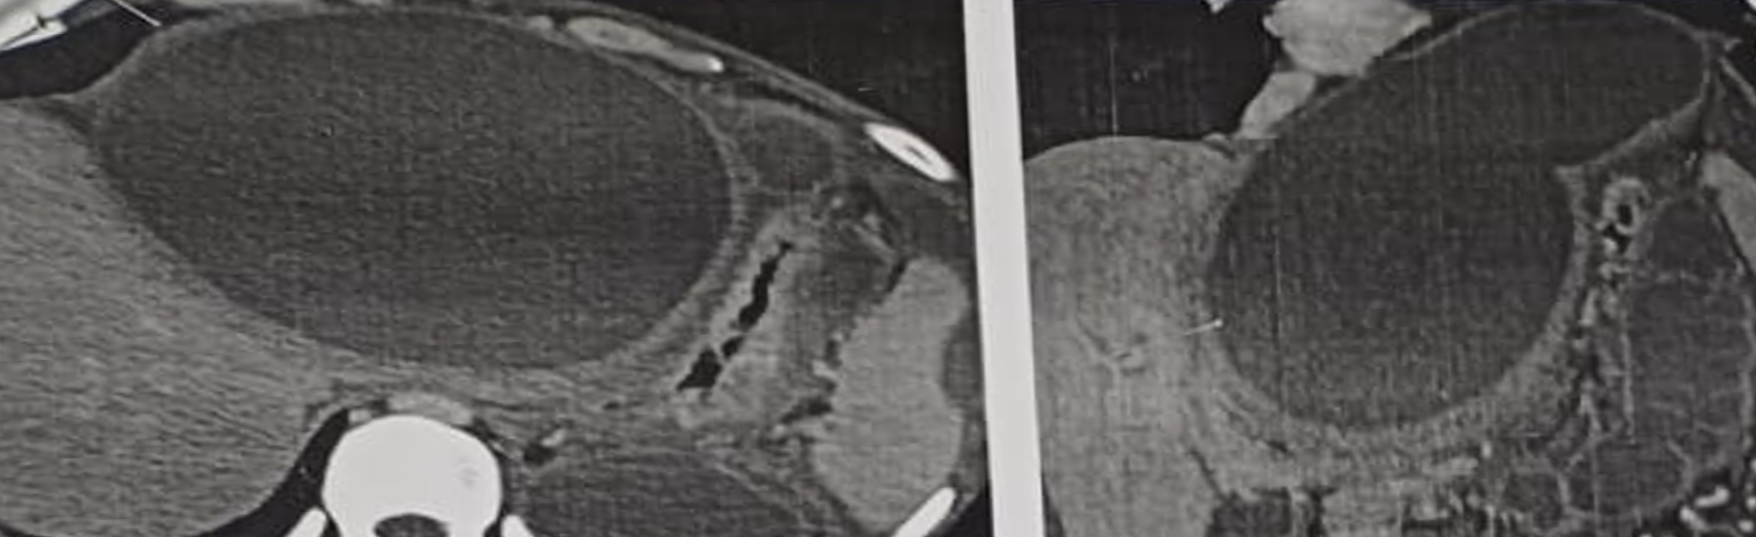

contrast-enhanced computed tomography of the abdomen was done which demonstrated a large thick-walled peripancreatic collection with extension into the perihepatic region and further into the perisplenic and gastrosplenic regions producing significant mass effect on the stomach. The posterior wall thickness of the collection measured approximately 5 mm. The collection extended up to the pancreatic tail and was closely related to a dilated pancreatic duct with suspected ductal communication. Additional thickwalled, intercommunicating collections were noted in the lesser sac and perinephric region causing mass effect on the left kidney and adrenal gland. Imaging also showed features of chronic calcific pancreatitis including an atrophic pancreas, a prominent pancreatic duct and intraparenchymal calcifications. Chronic splenic vein thrombosis was identified with multiple perisplenic, perigastric, peripancreatic, and fundal collaterals. The modified computed tomography severity index was 6/10, consistent with moderate severity (Figure 2).

Figure 2: Contrast-enhanced computed tomography (CECT) axial and coronal images showing a large, well-defined, thick-walled cystic lesion located in the prehepatic region anterior to the liver, causing significant mass effect on the stomach. The lesion is consistent with a pancreatic pseudocyst in an atypical prehepatic location, with communication to the pancreatic duct suggestive of chronic pancreatitis

Pancreatic pseudocysts are well-recognized complications of acute and chronic pancreatitis forming as encapsulated pancreatic secretions devoid of epithelial lining and typically confined to peripancreatic spaces. Most commonly, pseudocysts occur in the lesser sac, retroperitoneum or adjacent to the pancreatic head and body where fluid collects along natural fascial planes. These locations account for the majority of clinically encountered pseudocysts. However, the literature also reveals a spectrum of unusual pseudocyst localizations reporting extensions into the mediastinum, perinephric spaces, iliopsoas muscle and even the pleural cavity. These unusual locations underscore the ability of pancreatic secretions to extend into fascial planes far away from the original site of inflammation. These atypical pseudocyst presentations that may (including the prehepatic location observed in our case) are noteworthy because they may mimic unrelated pathologies such as hepatic cysts, subphrenic collection or subhepatic mass lesions.[11] In our patient, contrast-enhanced CT revealed a large thick-walled collection extending anterior to the liver, communicating with a dilated pancreatic duct and consistent with a mature pseudocyst in the setting of chronic pancreatitis. Accurate imaging analysis was critical in distinguishing this lesion from primary hepatic or subdiaphragmatic pathology.